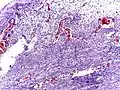

Pathology diagnosis of appendicitis can be made by detecting a neutrophilic infiltrate of the muscularis propria.

Classification of acute appendicitis based on gross pathology and light microscopy characteristics[62]

PatternGross pathologyLight microscopyImageClinical significance

Acute intraluminal inflammation None visible

• Only neutrophils in lumen

• No ulceration or transmural inflammation

Probably none

Acuta mucosal inflammation None visible

• Neutrophils within mucosa, and possibly in submucosa

• Mucosal ulceration

May be secondary to enteritis.

Suppurative acute appendicitis May be inapparent.

• Dull mucosa

• Congested surface vessels

• Fibropurulent serosal exudate in late cases

• Dilated appendix

• Neutrophils in mucosa, submucosa and muscularis propria, potentially transmural.

• Extensive inflammation

• Commonly intramural abscesses

• Possibly vascular thrombosis

Can be presumed to be primary cause of symptoms

Gangrenous/necrotizing appendicitis

• Friable wall

• Purple, green or black color

• Transmural inflammation

• Necrotic areas

• Extensive mucosal ulceration

Will perforate if untreated

Periappendicitis May be inapparent.

• Serosa may be congested, dull and exudative

• Serosal and subserosal inflammation, no further than outer muscularis propria to be called isolated

If isolated, probably secondary to other disease

Eosinophilic appendicitis None visible

• >10 eosinophils/mm2 in muscularis propria.

• No changes conforming to other types of appendicitis

Possibly parasitic, or eosinophilic enteritis.